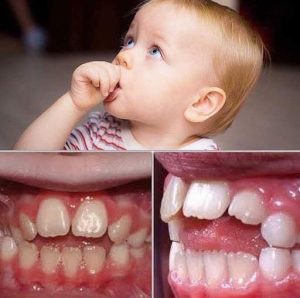

⚠️TẬT MÚT NGÓN TAY & NGUY HIỂM TIỀM TÀNG Ở TRẺ!

🆙Hiệu ứng hút ngón tay cái kéo dài:

• Mút ngón tay cái ngoài độ tuổi 4–5 không chỉ là một thói quen – nó có thể ảnh hưởng đến sự mọc hàm và vị trí răng. Áp suất liên tục làm thay đổi sự cân bằng giữa môi, lưỡi và xương phát triển.

• Theo thời gian, điều này có thể dẫn đến vết cắn hở, răng cửa nhổ, hàm trên hẹp, khó khăn về lời nói và nhu cầu chỉnh nha tăng cao sau này ở trẻ.

🔑Vấn đề hướng dẫn nha khoa từ sớm. Các chiến lược phá vỡ thói quen nhẹ nhàng, tăng cường tích cực và thăm khám nha khoa kịp thời có thể bảo vệ sự phát triển răng miệng bình thường và giảm sự phức tạp điều trị lâu dài.

💬 Đừng để chỉ vì những thói quen nhỏ hàng ngày ảnh hưởng tới tương lai con em chúng ta.